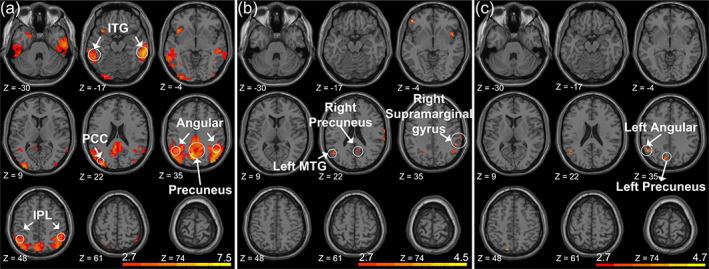

The discovery of preclinical Alzheimer's disease (preAD) provides a wide time window for the early intervention of AD. The coupling relationships between glucose and oxygen metabolisms from hybrid PET/MRI can provide complementary information on the brain's physiological state for preAD. In this study, we purpose to explore the change of coupling relationship among 27 normal controls (NCs), 20 preADs, and 15 cognitive impairments (CIs). For each subject, we calculated the Spearman partial correlation between the fractional amplitude of low-frequency fluctuations (fALFF) and the regional homogeneity (ReHo) from functional image (fMRI), and the standard uptake value ratio (SUVR) from [18F] fluorodeoxyglucose positron emission tomography ( F-FDG PET), in the whole-brain and default mode network (DMN) as a novel potential biomarker. The diagnostic performance of this biomarker was evaluated by the receiver operating characteristic analysis. Significant Spearman correlations between the FDG SUVR and the fALFF/ReHo were found in 98% of subjects. For the DMN-based biomarker, there was a significant decreasing trend for the preAD and CI groups compared to the NC group, whereas no significant difference in preAD based on whole-brain. The correlation ρ value for the FDG SUVR/ReHo showed the highest area under curve of the preAD classification (0.787). The results imply the coupling relationship changed during the preAD stage in the DMN area.

临床前阿尔茨海默病(preAD)的发现为 AD 的早期干预提供了广泛的时间窗口。杂交 PET/MRI 的葡萄糖和氧代谢的耦合关系可为 preAD 大脑的生理状态提供补充信息。在这项研究中,我们旨在探索 27 名正常对照(NC)、20 名 preAD 和 15 名认知障碍(CI)患者之间耦合关系的变化。对于每个受试者,我们计算了功能图像(fMRI)中低频振幅(fALFF)和局部一致性(ReHo)与 [18F]氟脱氧葡萄糖正电子发射断层扫描(F-FDG PET)中标准摄取值比(SUVR)之间的 Spearman 偏相关,作为一种新的潜在生物标志物,在全脑和默认模式网络(DMN)中进行。通过接收者操作特征分析评估了该生物标志物的诊断性能。在 98%的受试者中,FDG SUVR 与 fALFF/ReHo 之间存在显著的 Spearman 相关性。对于基于 DMN 的生物标志物,与 NC 组相比,preAD 和 CI 组表现出明显的下降趋势,而在全脑水平上,preAD 之间没有显著差异。FDG SUVR/ReHo 的相关 ρ 值显示了 preAD 分类的最高曲线下面积(0.787)。结果表明,在 DMN 区域,preAD 阶段的耦合关系发生了变化。